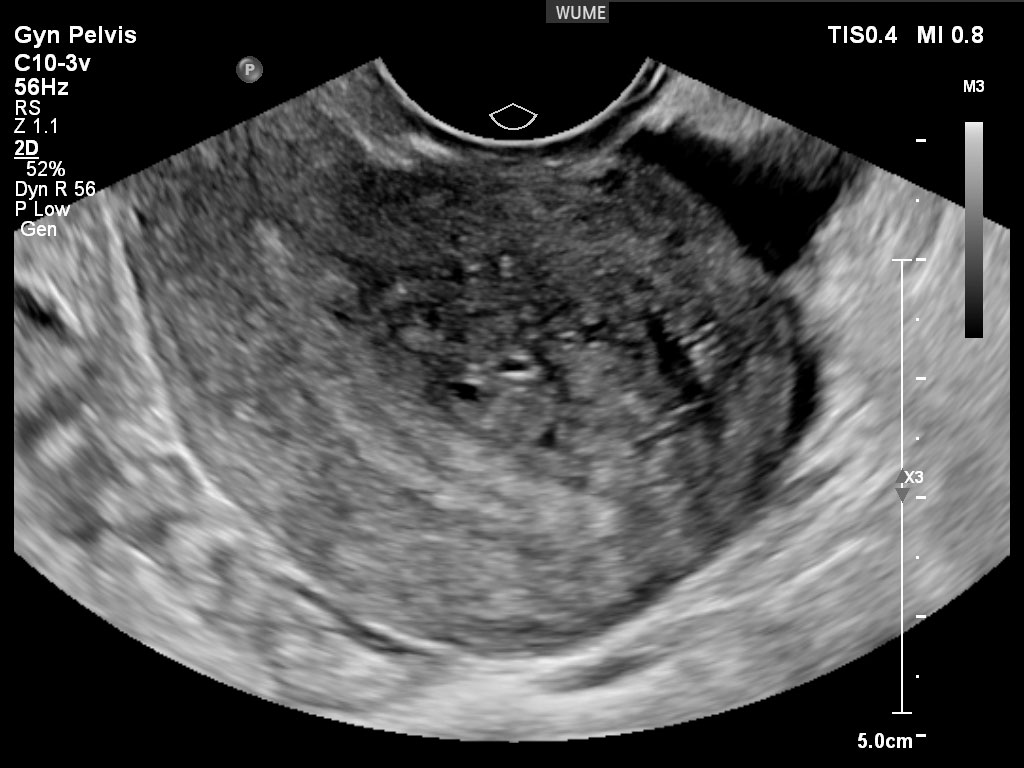

کیست های تخمدان

تخمدان ها اندام های فعالی هستند که به طور طبیعی در طول چرخه قاعدگی "کیست" کوچک ایجاد می کنند. اینها کیست هایی با عملکرد طبیعی تخمدان هستند. این کیست های طبیعی معمولاً به راحتی قابل تشخیص هستند. کیستهای مهمتر را میتوان در طول اسکن تشخیص و ارزیابی کرد و هر یافته مهمی را که در گزارش برای پزشک شرح داده شد و همچنین در زمان سونوگرافی با شما در میان گذاشت.